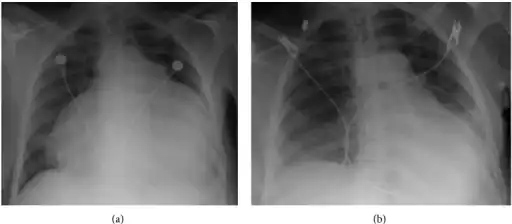

a) Cardiomegaly due to pericardial fluid b)after pericardial fluid drainage.